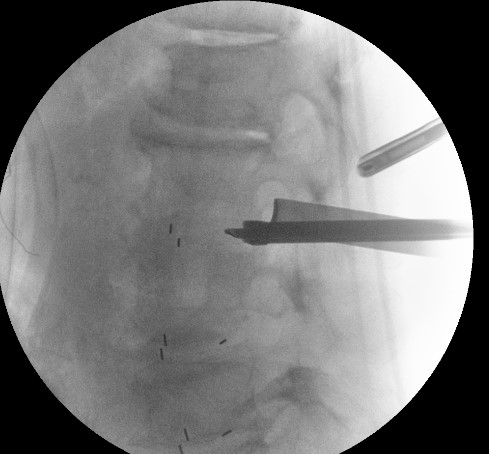

양방향 척추 내시경을 통해

디스크 하나하나에

케이지를 삽입하여

추간공 간극을 벌리는 작업을 진행하였구요

수술을 마치고는

4마디에 대해서

최소침습 나사못 고정으로

마무리를 진행하였구요